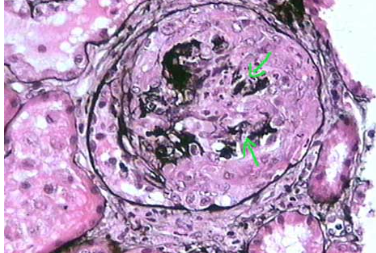

DX & Tinción:

A

Esclerosis global

* tinción cafe de plata

* Clase 6~nefropatía terminal o escleriorsis avanzada.